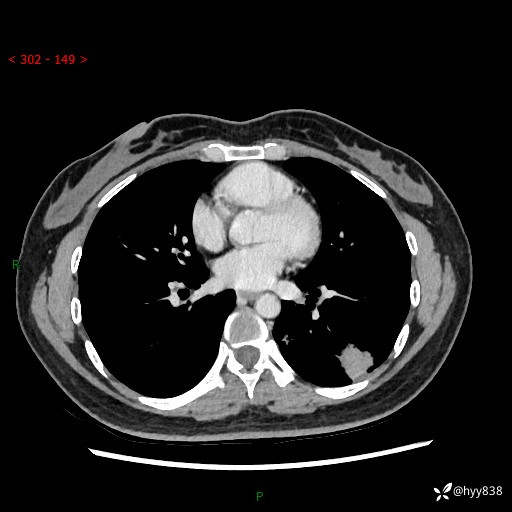

【患者信息】:36岁/女

【主诉】:左侧下胸部阵发性疼痛2周,乏力1周

【现病史及既往史】:患者自诉2周前饮酒后出现左侧下胸部阵发性疼痛,不随呼吸改变,无咳嗽咳痰、头晕头痛、咳血、呼吸困难等不适,于当地第一人民医院查胸部CT提示肺部感染,随后前往我院门诊给予抗感染(左氧氟沙星)治疗1周,自诉胸痛较前好转,感乏力、头晕,偶尔干咳,无咳痰,无发热、畏寒、胸闷、咯血、四肢酸痛、腹泻、腹痛等不适,门诊复查胸部CT提示:左肺下叶感染,病灶较前增加增大,遂以“肺部感染”收入我科。 起病以来,患者精神、饮食、睡眠可,大小便正常,体力体重无明显变化。

【检查】:胸部CT增强(外院平扫)